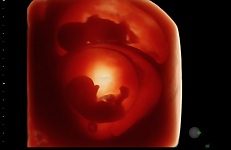

Клинические изображения VOLUSON S10:

- HDlive в 3D и 4D - режим перемещаемого виртуального источника освещения - "виртуальная фетоскопия"